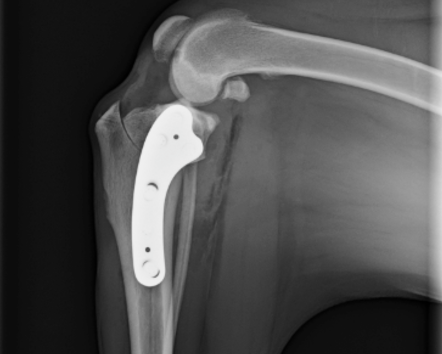

Our introductory TPLO workshops are designed to give veterinarians a solid foundation in the procedure from day one. You’ll learn how to evaluate patients, plan and execute the surgery step by step using the BioCurve TPLO plate, and understand the principles behind successful outcomes. Through guided lectures and hands-on cadaver labs, you’ll gain the technical confidence and clinical judgment needed to approach your first TPLO cases with confidence.